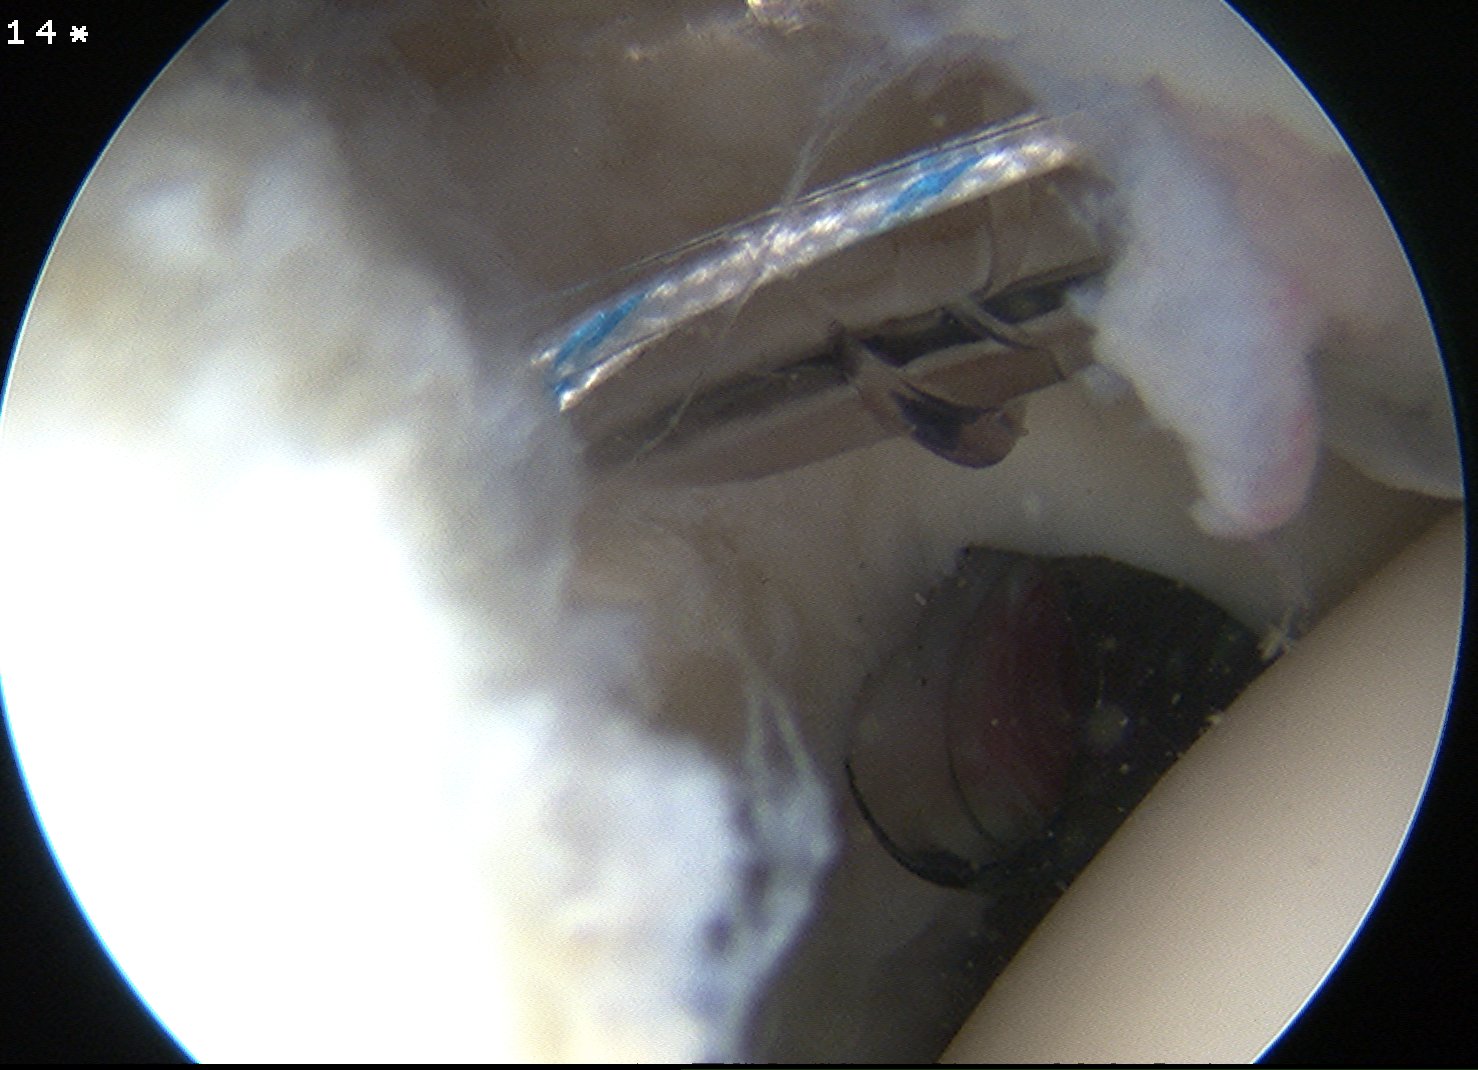

Subacromial space

Portals

| Posterior | Lateral subacromial portal |

|

Redirect posterior portal Under acromion |

Midportal clavicle |

| Usually viewing portal |

Rotator cuff repair / Subacromial decompression Distal clavicle resection |

![]() |